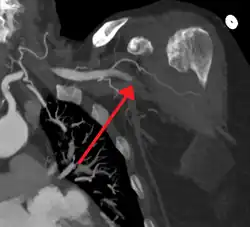

| Acute embolism to the right femoral artery resulting in ischemia | |